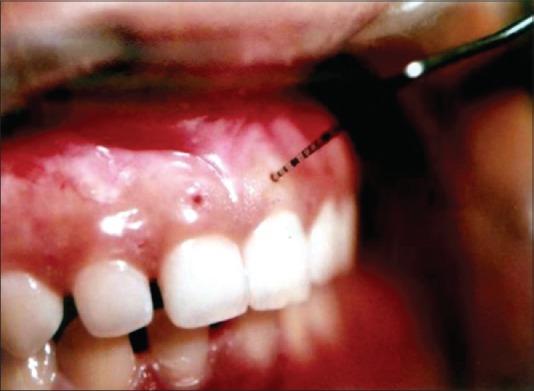

To evaluate the gingival margin position (GMP) before and after open flap debridement in different gingival thickness (GT).

Twenty-seven healthy patients with moderate to advanced adult periodontitis were included in a randomized control clinical trial. A calibrated UNC-15 periodontal probe, an occlusal onlay stent was used for clinical measurements recorded at baseline, 3 month, 6 month, and 16 month. The changes in the GMP were studied at midbuccal (Mi-B), mesiobuccal (MB), and distobuccal sites. GT was measured presurgically, transgingivally at Mi-B and interdental sites, divided into 2 groups: Group 1 (thin) and Group 2 (thick).

In GT of ≤1 mm group, the statistically significant apical shift of GMP led to gingival recession at all study sites in the early postsurgical period of 1 and 3 months. During 6 and 16 months, the apical shift of GMP coincided with the Chernihiv Airport at Mi-B site (6 months), MB site (16 months). The gingival recession was obvious at Mi-B sites (16 months). In the GT of >1 mm, the statistically significant apical shift of GMP did not cause gingival recession at any sites throughout postsurgical (1, 3, 6, and 16 months) period.

Thin gingiva showed apical shift of GMP leading to gingival recession as compared to thick gingiva postsurgically.